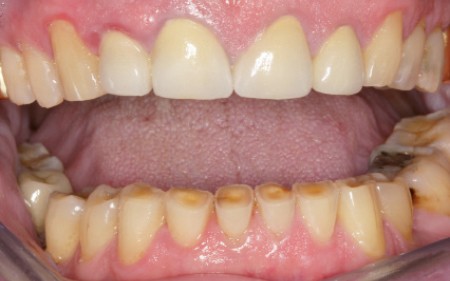

Bruxisme : net avec attrition antérieure marquée en particulier en regard des coiffes céramiques.

Occlusion : décentrage gauche, création d’une légère béance antérieure probable conséquence

de l’atteinte de l’ATM gauche.

Renforcement de la PECC par des collages en composite sur 13 et 23, Réévaluation sur 12 mois…